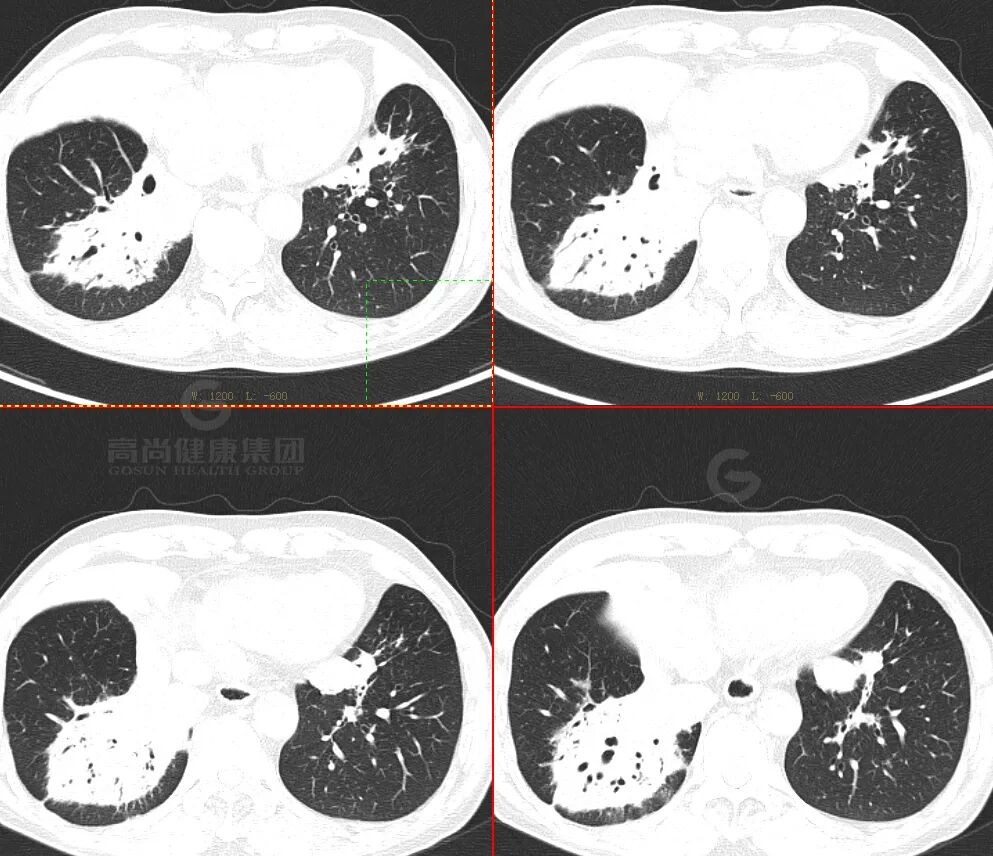

PET/CT 图像

痰培养提示

产酸克雷伯菌感染

影像特征:

外周分布 (起源外围、由外向内蔓延)

实变和磨玻璃阴影

病理性支气管充气征

实变内有密度较低、强化较低区

「假空洞」/「蜂窝」征

周围小结节,树芽征少

间质增厚

胸膜改变:糊墙征